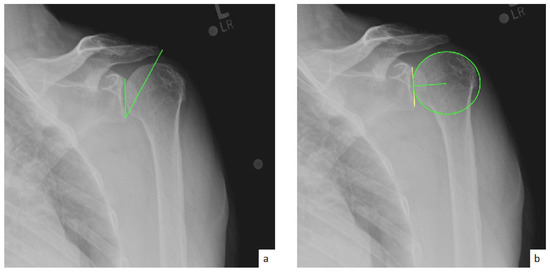

AHD was measured by calculating the perpendicular distance between the most lateral portion of the undersurface of the acromion and a line parallel to the superior border of the greater tuberosity [21] (Figure 1). LHO was measured by determining the distance from the AHD line to the most lateral projection of the greater tuberosity [21] (Figure 2). LSA was measured by drawing a line from the superior glenoid tubercle to the most lateral border of the acromion and a second line from the most lateral border of the acromion to the most lateral border of the greater tuberosity. The angle between these two lines formed the LSA [20] (Figure 3a). DSA was measured by drawing a line between the most lateral border of the acromion and the superior glenoid tubercle and drawing a second line to connect the superior glenoid tubercle with the most superior border of the greater tuberosity. The angle between these two lines formed the DSA [20] (Figure 3b). Glenoid and baseplate were determined as the angle between the floor of the supraspinatus fossa and the glenoid fossa [25] (Figure 4). COR was measured by determining the best fit circle flush to the articular surface, identifying the center of the circle in the humeral head, and then measuring the distance of the perpendicular line between the center of the humeral head and the midpoint of the line connecting the superior and inferior glenoid tubercles [24] (Figure 5b). CSA was measured by a line from the superior pole to the inferior pole of the glenoid and a line from the inferior pole to the lateral edge of the acromion [26] (Figure 5a). In addition, scapular notching was graded according to the Nerot–Sirveaux classification and severity of preoperative cuff tear arthropathy was evaluated according to the Hamada classification [27,28].

Figure 4.

(a) Glenoid inclination (green angle); (b) baseplate inclination (green line).

Figure 5.

(a) Critical shoulder angle (CSA; green angle); (b) center of rotation (COI; green line).